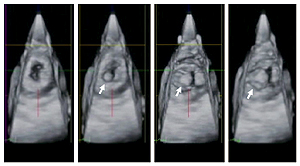

僧帽弁口に生じた感染性心内膜炎の疣贅を心尖方向から3D心エコーで観察した.

収縮期(左端の図)には疣贅は図の奥の左房に存在しているが,拡張期(右の三つの図)には僧帽弁を通って左室内に移動してくる(矢印)ことが分かる.